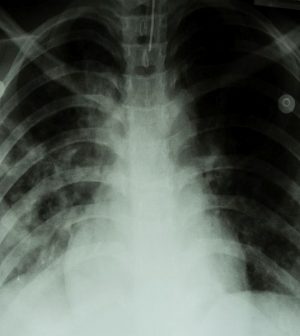

Tuberculosis (TB), a bacterial lung disease, is potentially fatal, but it is preventable and curable in children and teens.